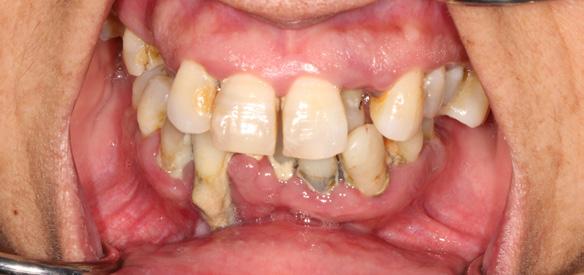

New Teeth In One Day, A state-of-the-art technique performed by Dr. Gregory

Do you ever catch yourself missing the familiar comfort of your own teeth? Frustrated with dentures that just don’t look or feel right? Or maybe, the mere thought of dentures has kept you from seeking treatment, fearing a life without the authenticity of your natural smile?

Welcome to Dr. Gregory’s “Teeth In One Day” solution – a transformative experience tailored just for you. This isn’t about just replacing teeth; it’s about reviving the confidence of your natural smile.

Imagine walking into Dr. Gregory’s cozy office, where you’re gently sedated for a worry-free procedure. Once you’re comfortably at ease, we replace any existing teeth with 4 to 6 state-of-the-art dental implants, precisely set into your jawbone. But here’s where the magic truly happens: a set of teeth, custom-

crafted uniquely for you, is secured onto these implants. This isn’t a temporary fix. These teeth will not only look, feel, and function like your natural teeth, but they’ll also stay with you, day in and day out – no nightly removals, no adjustments. Simply a new, permanent smile that’s unmistakably yours.

Why choose Dr. Gregory’s Teeth In One Day?

Commitment Beyond Procedures: We provide a lifetime of follow up care and personal accountability for our work. We won’t refer you out of our practice after your surgery is complete. We see you at least once a year to check our work and evaluate the health, function, and esthetic of your implants and your new teeth. You become part of our patient family.

Double the Care, Double the Quality: We provide you with two full sets of new teeth. Other practices frequently offer only one set of all-plastic (acrylic) teeth the day of surgery. We believe it is not acceptable to deliver an allplastic set of teeth as a final solution (plastic is porous and grows bacteria and fungus, is rough and difficult to clean). We provide an additional final set of teeth made of titanium with esthetic overlay or made of zirconia (ceramic). These materials are appropriate to protect the implants from infection and to provide a durable chewing solution and a beautiful long term result.

Unwavering Quality Standards: Your smile deserves the best. And we make no compromises there. We use quality implants and authentic implant parts. Dental implants are made by various manufacturers and are not all equal in quality or research support. Implants backed by years of research cost ten times what “knock off” implants can cost. Authentic parts that are fabricated to fit those implants are also more costly. We believe it’s absolutely worth the cost to have quality implants and implant parts used during surgery in an effort to minimize implant failures.

Tailored Just for You: No two smiles are the same, and neither should be the approach to care for them. We provide a customized surgery strategy for every patient. There is no one surgical plan that fits every patient. Every patient has a different dental history and a different personal story. There are many treatment options and we feel proud to offer a wide variety of techniques. We listen to our patients and help them arrive at a plan that makes sense for their dental condition, their emotional needs, and their financial possibilities.

Say goodbye to the inconveniences of conventional dentures and embrace a renewed, authentic smile with Dr. Gregor where you’re not just another patient; you’re family.

We offer comprehensive family dentistry and specialist services under one roof including preventive family dental cleanings, fillings, crowns, veneers, oral surgery, adult orthodontics, and periodontics. We also offer in-house dental insurance and work with employer insurance plans. We have a variety of financing options available.

Before & After Before & After